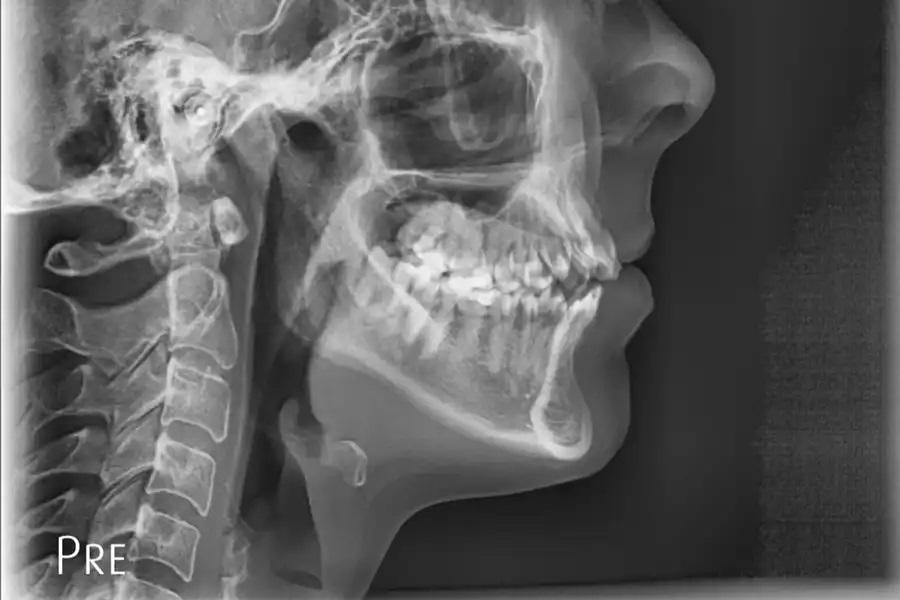

Повторная оценка по данным панорамной рентгенографии и цефалометрии используется для подтверждения интрузии боковых зубов без резорбции корней или изменений в области пазух, улучшения наклона верхних резцов в пределах костной ткани, изменений профиля губ, соответствующих авторотации пр. ч. с., и благоприятных скелетных параметров. (фото 17 – 20)

Фото 18. Панорамная рентгенограмма через 15 месяцев после завершения лечения. Выявлено выраженное двустороннее дентоальвеолярное ремоделирование в области премоляров и моляров. Альвеолярный отросток вместе с зубами смещен краниально, что соответствует успешной интрузии боковых зубов и авторотации нижней челюсти пр. ч. с. Уровень краевой кости и прикрепления остался неизменным, признаков резорбции корней или изменений в области пазух не выявлено, что свидетельствует о стабильной костной адаптации и сохранности пародонта.

Фото 19. Цефалометрическая рентгенограмма до лечения. Базовая латеральная телерентгенограмма, демонстрирующая исходные скелетные и зубные соотношения. Верхнечелюстная плоскость и окклюзионная кривая имели выраженный наклон, с акцентированной кривой Шпее, тенденцией к открытому прикусу и уменьшенными значениями вертикального и сагиттального перекрытия.

Фото 17. Панорамная рентгенограмма до лечения. Базовое изображение, демонстрирующее исходные дентоальвеолярные взаимоотношения. В области премоляров и моляров отмечается нормальный уровень краевой кости и прикрепления, служащий ориентиром для последующего сравнения.